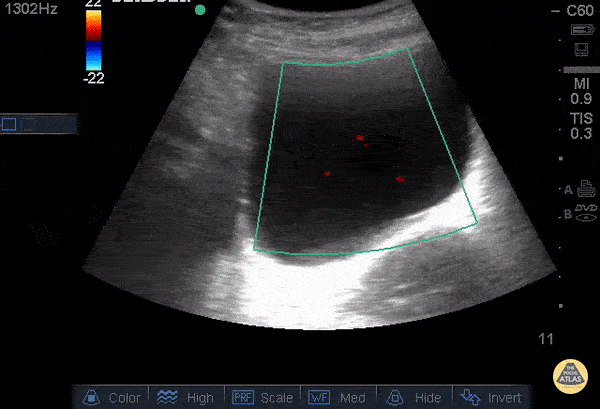

An 88 year old female with history of renal stones presented with flank pain and a nonfunctioning nephrostomy tube. Bedside US showed severe hydronephrosis (see other image). Using color Doppler over the bladder, the ureteral jets were evaluated. The diagnosis of obstruction was made, due to the absence of the right jet. Dr. Steven Greenstein, Dr. Maan Al Dubayan, Dr. Andrew Aherne - Kings County Emergency Medicine